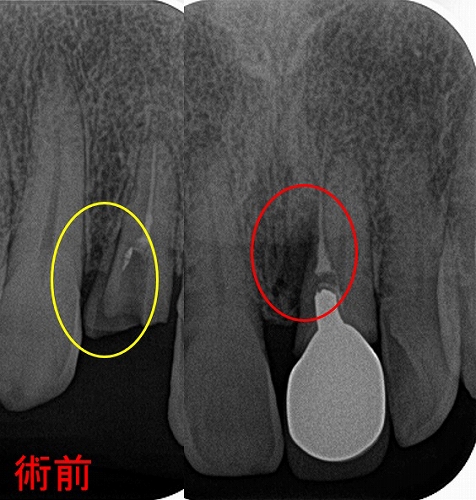

ん~、水酸化カルシュウムが歯の外に押し出しているように見えます。

私はこの歯歯根破折だと判断し、抜歯させてもらいましたが。

抜いた歯には根尖病変内に水酸化カルシュウム

国内で販売されている根管貼薬剤の水酸化カルシュウは殆ど油なので

歯の外に押し出しても吸収して骨に変わることはありません。